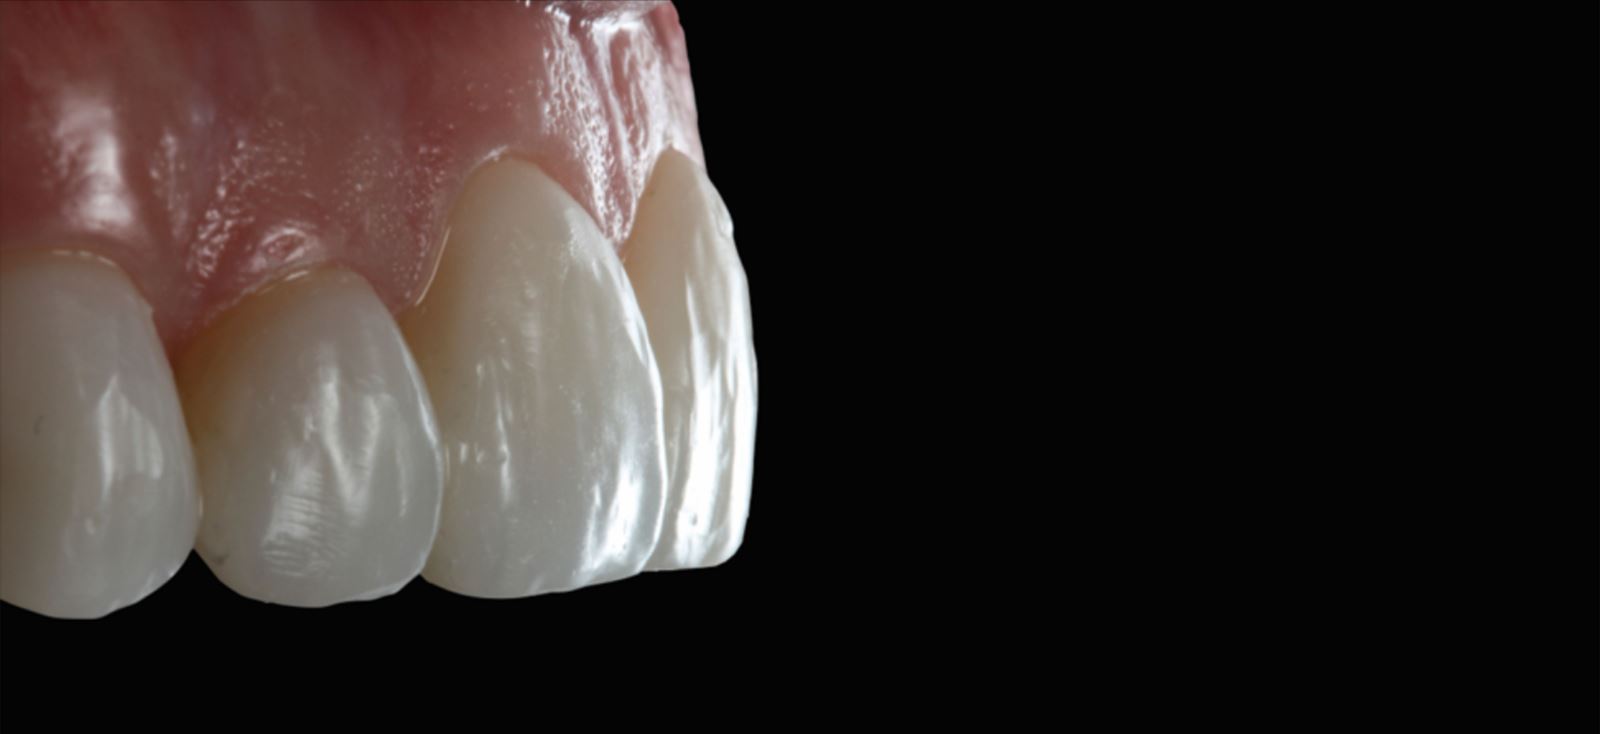

Leštění a příprava na cementaci:

Fazety byly konturovány a vyleštěny pomocí lešticí sady Jiffy™ Natural, čímž byly připraveny k cementaci.

Modelace anatomie fazet

K modelaci anatomie fazet byly použita diamantová brouska ve tvaru míče na ragby a dlouhý tenký diamantový brousek. K vytvoření linií Retzia (SR lines) byla použita lobulární diamantový brousek (segmentovaný, „laločnatý“ tvar). Počáteční leštění proběhlo s Jiffy™ Natural, finální lesk byl dosažen přípravkem Ultradent™ Diamond Polish Mint a Jiffy™ Goat Hair Brush (není dostupný v Evropě), aby nedošlo k odstranění terciární anatomie.